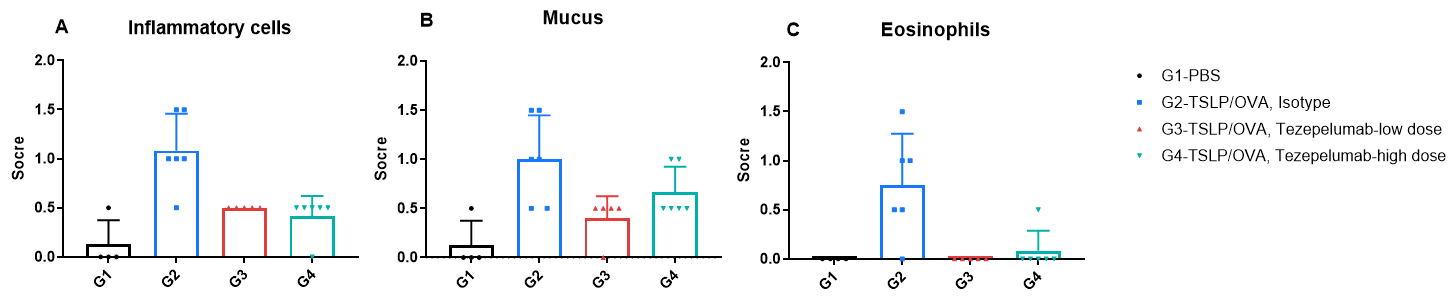

H&E staining and histopathological scoring of lung tissue in TSLP/OVA-induced asthma model of TSLP and TSLP receptor humanized (B-TSLP/TSLPR) mice. Compared to G1 (PBS-treated controls), G2 (TSLP/OVA + isotype) mice exhibited hallmark asthma pathology, including vascular and peribronchial mixed inflammatory cell infiltration (b) and mucus accumulation (a) in bronchi. Tezepelumab treatment in G3 (low dose) and G4 (high dose) reduced airway inflammation and mucus secretion in a dose-dependent manner. Increased inflammatory cell infiltration, mucus production, and eosinophil presence were observed in G2, all of which were attenuated by anti-TSLP therapy, supporting the efficacy of tezepelumab in this allergic asthma model.